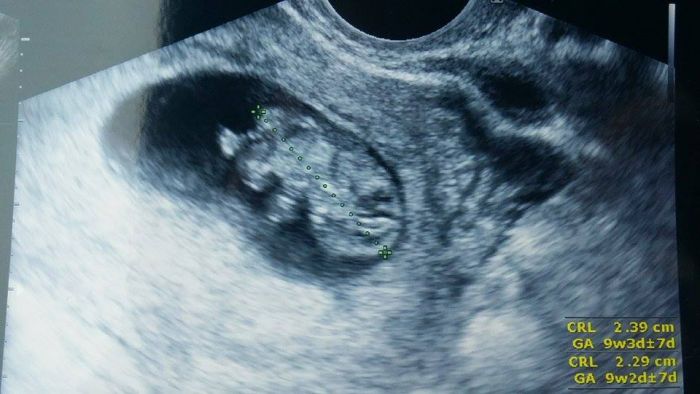

holky, dnes jsem byla na kontrole. Dostala jsem občanku na miminko a byla to fakt nádhera, protože tam sebou pořád mrskal a mával ručičkama. Fotka nádherná. Prý je to pořádný cvalík :-D jinak měříme skoro 2,5cm a odpovídáme 9+3 a rosteme prý podle tabulek. Takže jsem hrozně šťastná a spokojená.